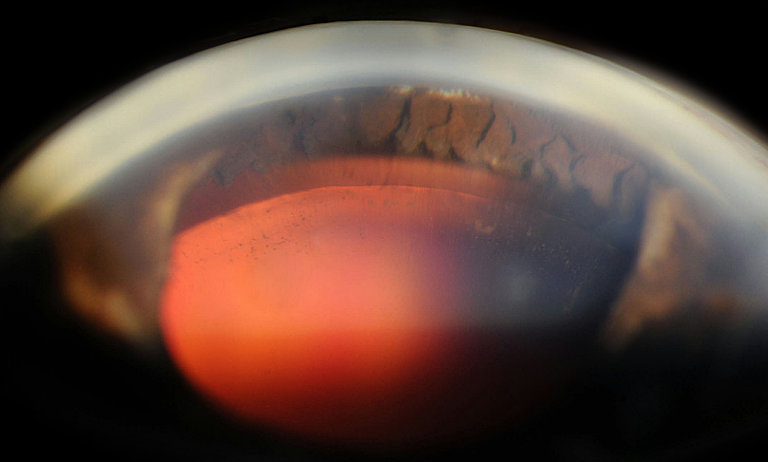

Iridectomy

Presented by James Gilman, BSc, CRAThis photograph received 2nd Place in the category "Gonio Photography" and was displayed at the 2024 ASCRS/OPS Society Exhibit.